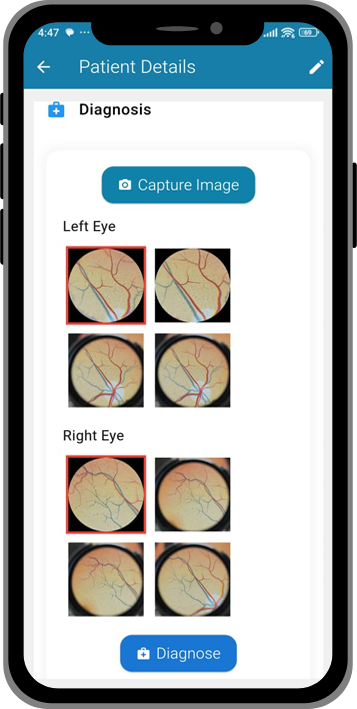

1. Capture

A healthcare worker attaches Lunera to a smartphone and takes retinal images.

2. Analyze

Lunera’s AI model scans the images for signs of DR & other retinal conditions.

3. Report

Instant results appear on the app, stored securely for doctors & patients.